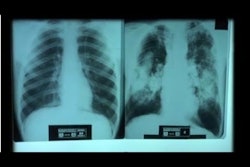

The U.S. Department of Labor’s Occupational Safety and Health Administration (OSHA) announced a proposed rule aimed at curbing lung cancer, silicosis, chronic obstructive pulmonary disease and kidney disease in America’s workers. The proposal seeks to lower worker exposure to crystalline silica, which kills hundreds of workers and sickens thousands more each year. After publication of the proposal, the public will have 90 days to submit written comments, followed by public hearings.

Once the full effects of the rule are realized, OSHA estimates that the proposed rule would result in saving nearly 700 lives per year and prevent 1,600 new cases of silicosis annually.

“Exposure to silica can be deadly, and limiting that exposure is essential,” said Dr. David Michaels, assistant secretary of labor for occupational safety and health. “Every year, exposed workers not only lose their ability to work, but also to breathe. This proposal is expected to prevent thousands of deaths from silicosis - an incurable and progressive disease - as well as lung cancer, other respiratory diseases and kidney disease. We’re looking forward to public comment on the proposal.”